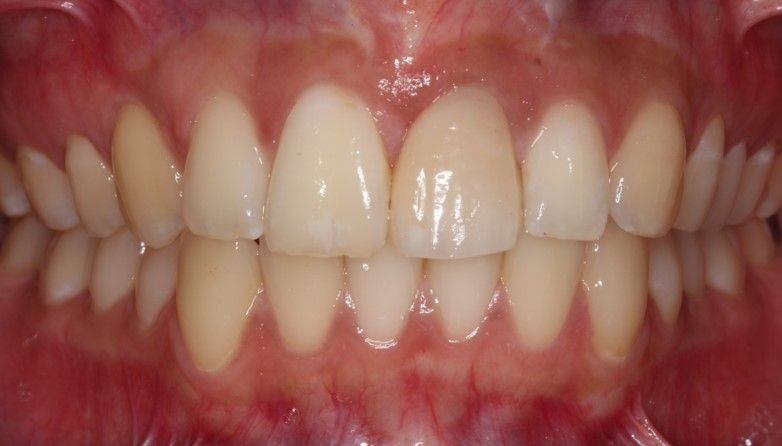

Case 2 - Lower incisor replaced with dental implant crown